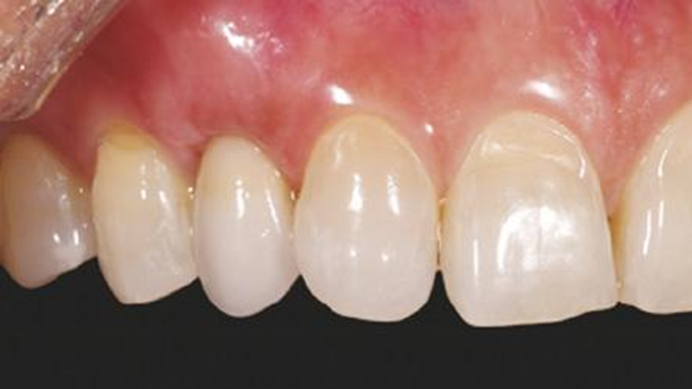

Clinical case: Patient-centered approach: treatment strategy for Root Membrane Technique & delayed implant placement

- Courtesy of Dr. Yoshiharu Hayashi, Japan -

“Advanced IntermezzoTM – one-piece solution for immediate placement & esthetic result in anterior region or narrow space.”